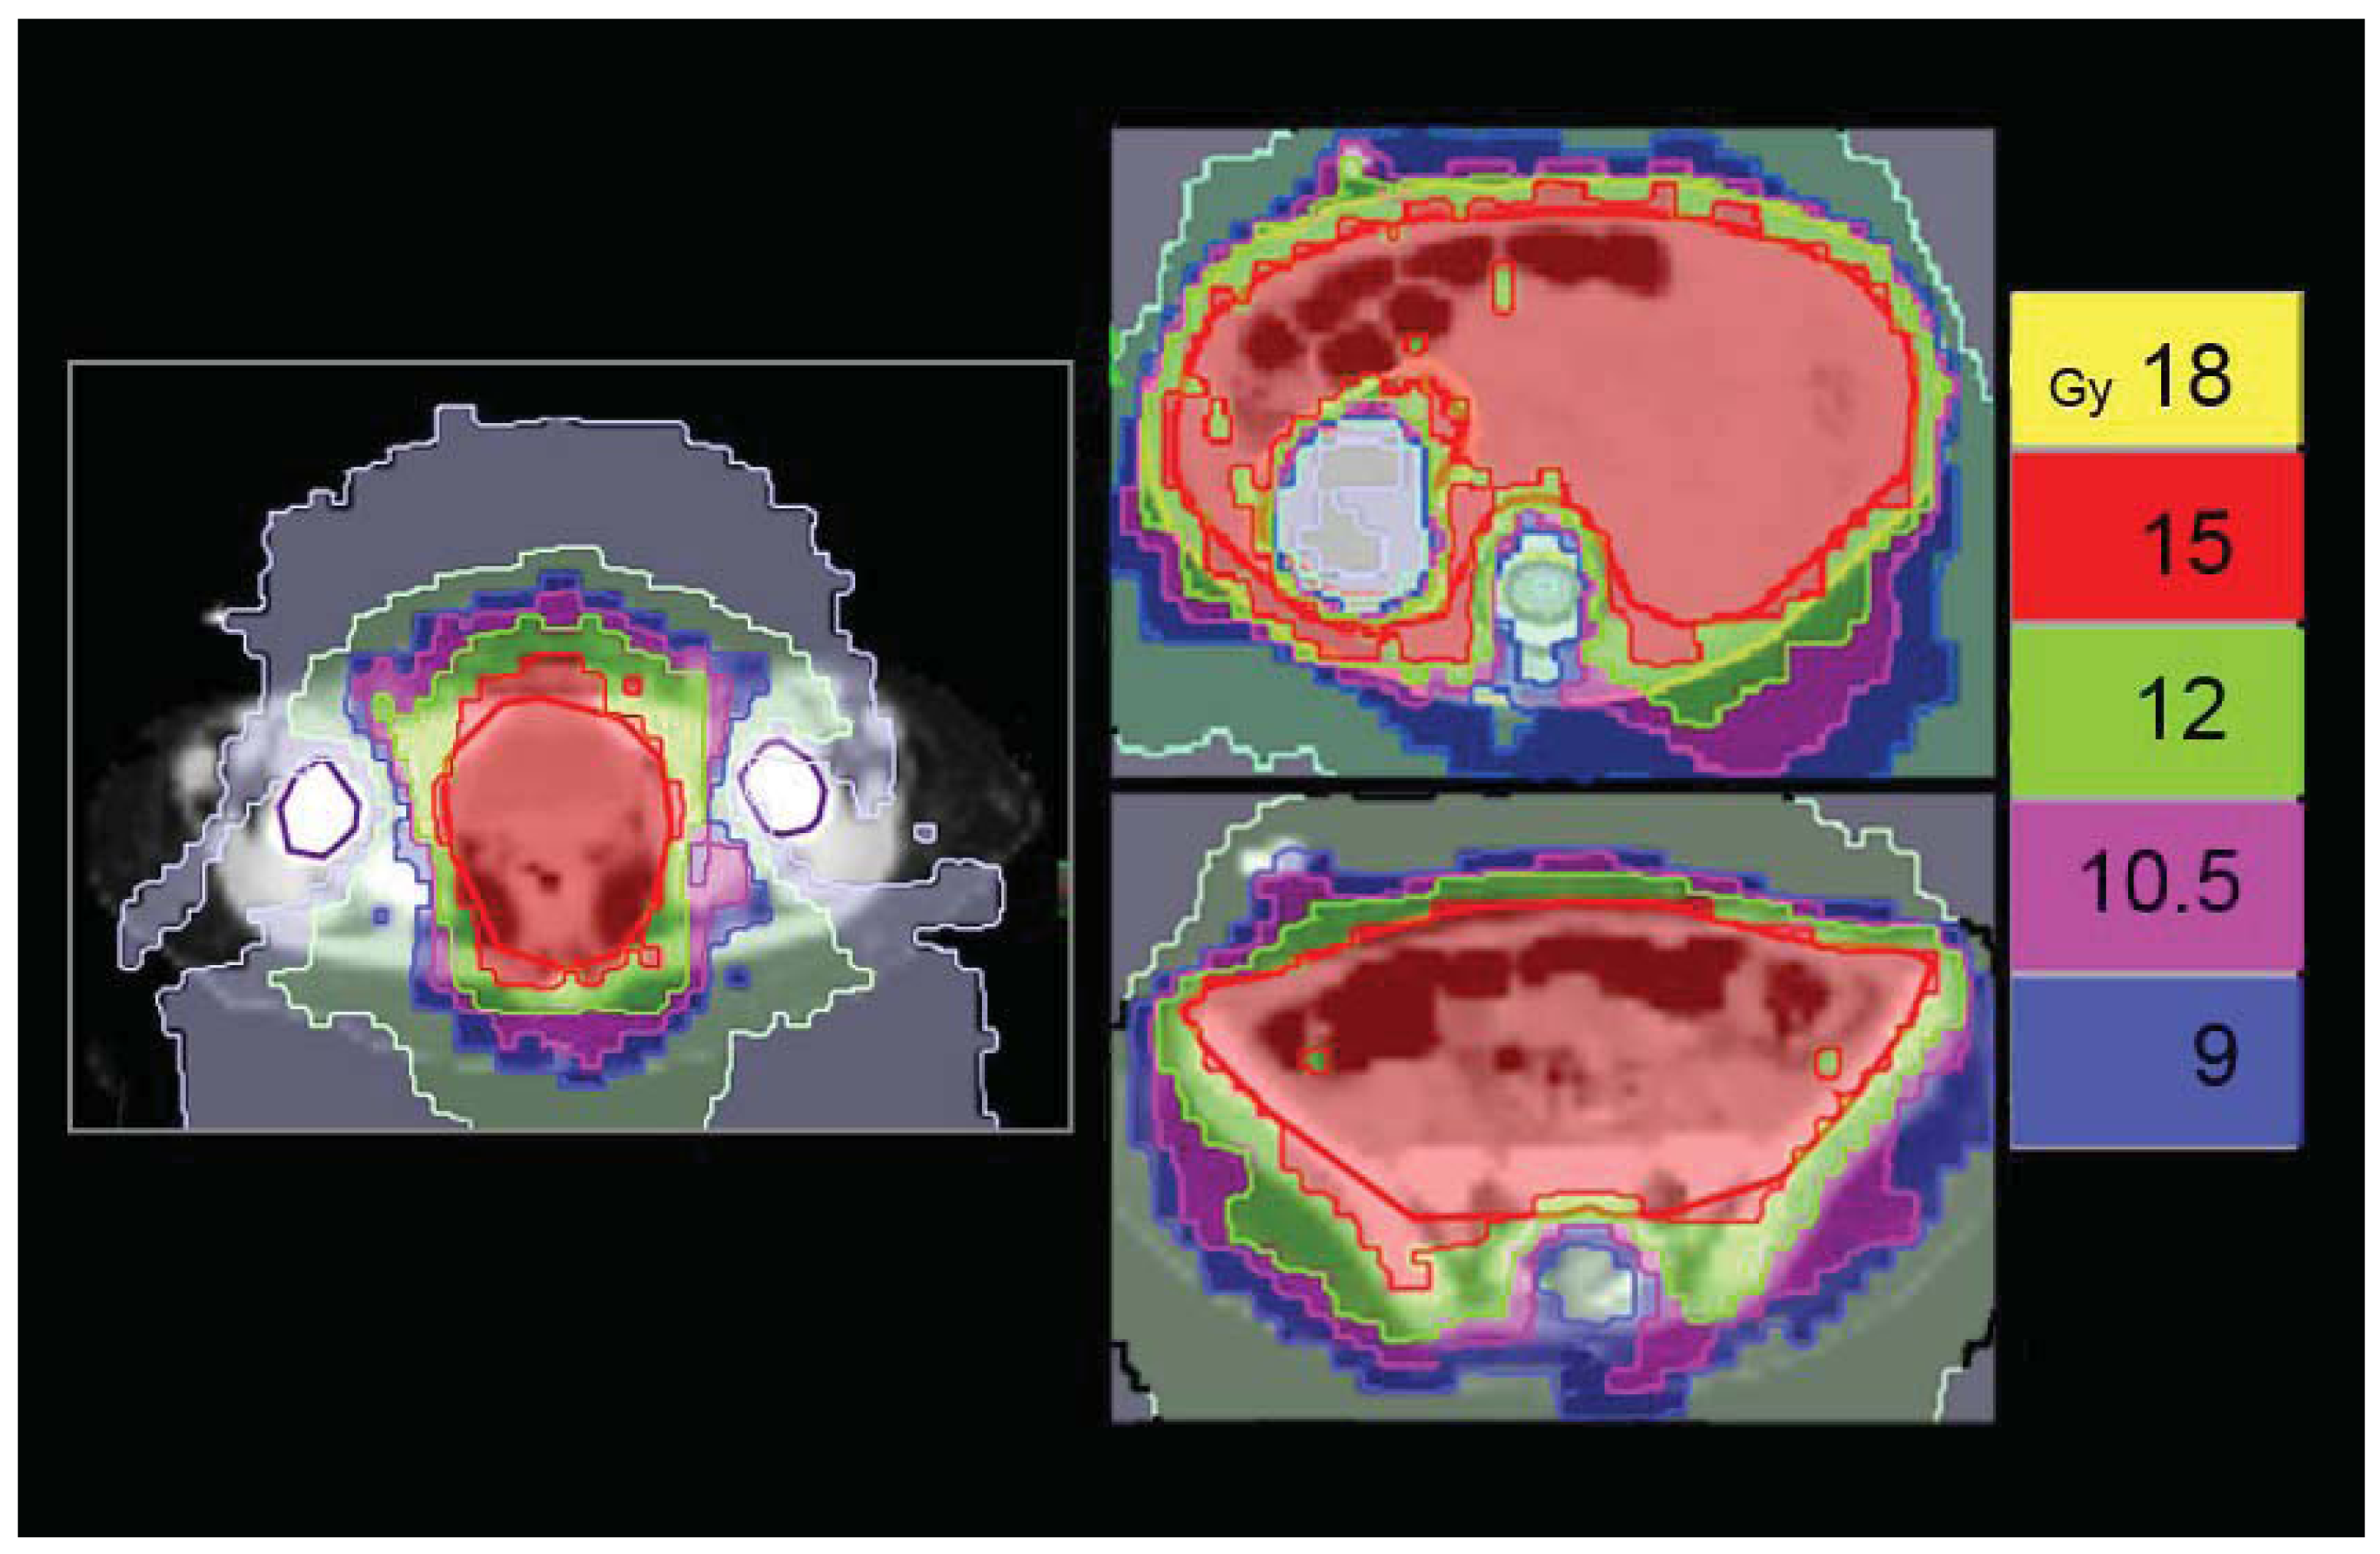

Irradiation of the pleural cavity represents a special challenge for radiotherapists because every conventional technique determines the risk of delivering high doses to the involved lung. Even if this treatment is mostly applied in the adult population with mesothelioma, sometimes also pediatric age cases of soft tissue tumors can involve the entire pleura. We applied HT to an adolescent patient affected by PNET (primitive neuroectodermal tumor) of the right pleural cavity with multiple nodular localizations and, after chemotherapy, a residual bulky disease along the base of the diaphragm. The patient was simulated in a supine position with arms overhead and fixed with a vacuum bag. The prescription to the right pleural PTV was: first phase, 36Gy in 20 fractions with a simultaneous integrated boost of 42 Gy in 20 fractions to the post-chemotherapy residual disease [Figure 8(a)]; second phase, 10 Gy in five fractions (total dose 52 Gy) delivered only to the shrinking residual costal-diaphragmatic tumor [Figure 8(c)]. The planning was built with the following constraints: mean total lung dose <20 Gy; V20 Gy total lung <30–35%; left healthy lung, all volume <15 Gy, V5 Gy <50%; heart V 20Gy <50%. A tune structure was built in the central part of the affected lung with a dose constraint of 20 Gy [24]. The result was quite good both in terms of PTV coverage and the sparing of the contra-lateral lung and other OARs [Figure 8(a)]. The mean total lung dose and the V5 Gy were 15.9 Gy and 50%, respectively. The mean dose for the affected lung was 29.1 Gy. The maximum dose, the mean dose and the V5 Gy for the healthy lung were 10.5 Gy, 3.4 Gy and 3.8%, respectively. The maximum dose, the mean dose and the V20 Gy for the heart were 38.2 Gy, 15.5 Gy and 22%, respectively [Figure 8(b)]. The plan was initially defined on the basis of pre-RT imaging, but this could not accurately reflect the degree of normal lung exposure during all treatment. For this reason, while monitoring tumor shrinkage with daily MV-CT, we planned the second treatment phase on the basis of MV-CT acquisition, applying an adaptive therapy to try to further reduce any exposure to the normal lung [Figure 8(c)]. The patient is in complete remission after 42 months from end of RT. He developed a transient radiation pneumonitis in the right lung during the first year, requiring steroid support.